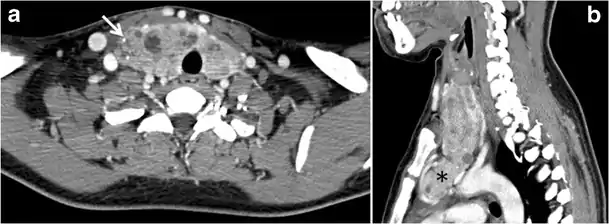

Fig. 8. A 48-year-old male patient post total thyroidectomy with PTC recurrence. a Transverse greyscale ultrasound of the neck demonstrates a left thyroid bed heterogeneous, predominantly hypoechoic irregular lesion with calcifications (white arrow). b A spot image of iodine 123 total body scan of the neck demonstrate a focus of abnormal radiotracer uptake at the left thyroid bed (Black arrows) between the annotated markers. c Enhanced axial CT scan of the neck demonstrates an enhancing large left thyroid bed mass (white arrow) with no calcifications. The lesion exerts a mass effect on the oesophagus (black arrow) and is inseparable from the trachea.[1]

Fig. 13. A 27-year-old female patient known to have goiter. a, b Axial and sagittal enhanced CT scan images of the neck demonstrate a heterogeneously enhancing, enlarged thyroid gland with scattered calcifications (white arrow), cystic changes, and substantial retro-sternal extension (black asterisks). No lymphadenopathy or substantial airway narrowing.[1]